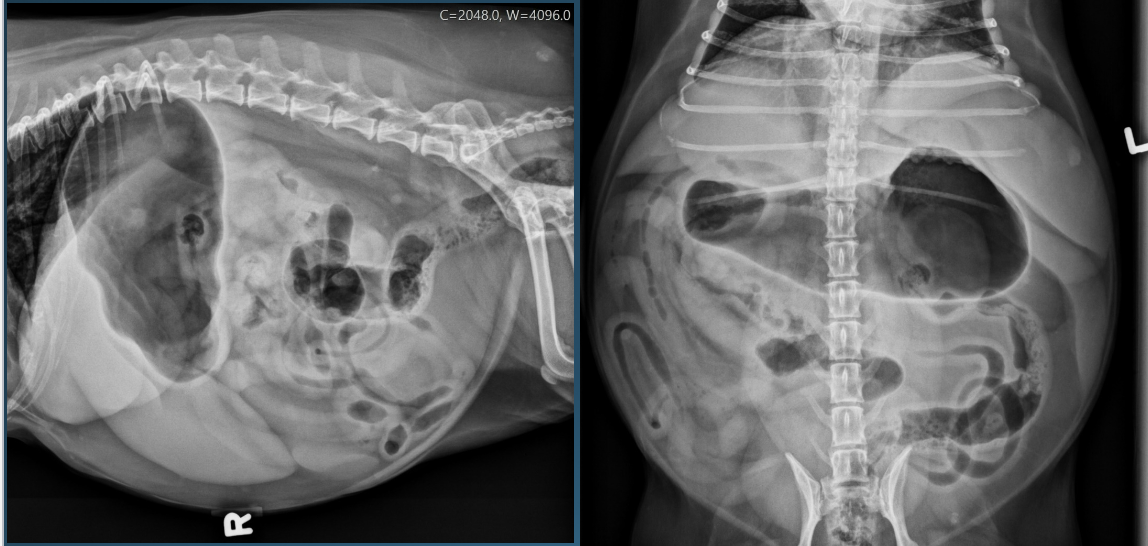

What is shown in these images?

generalized hepatomegaly:

-pendulous abdomen with no fluid accumulation

-likely hyperadrenocorticism/cushing’s